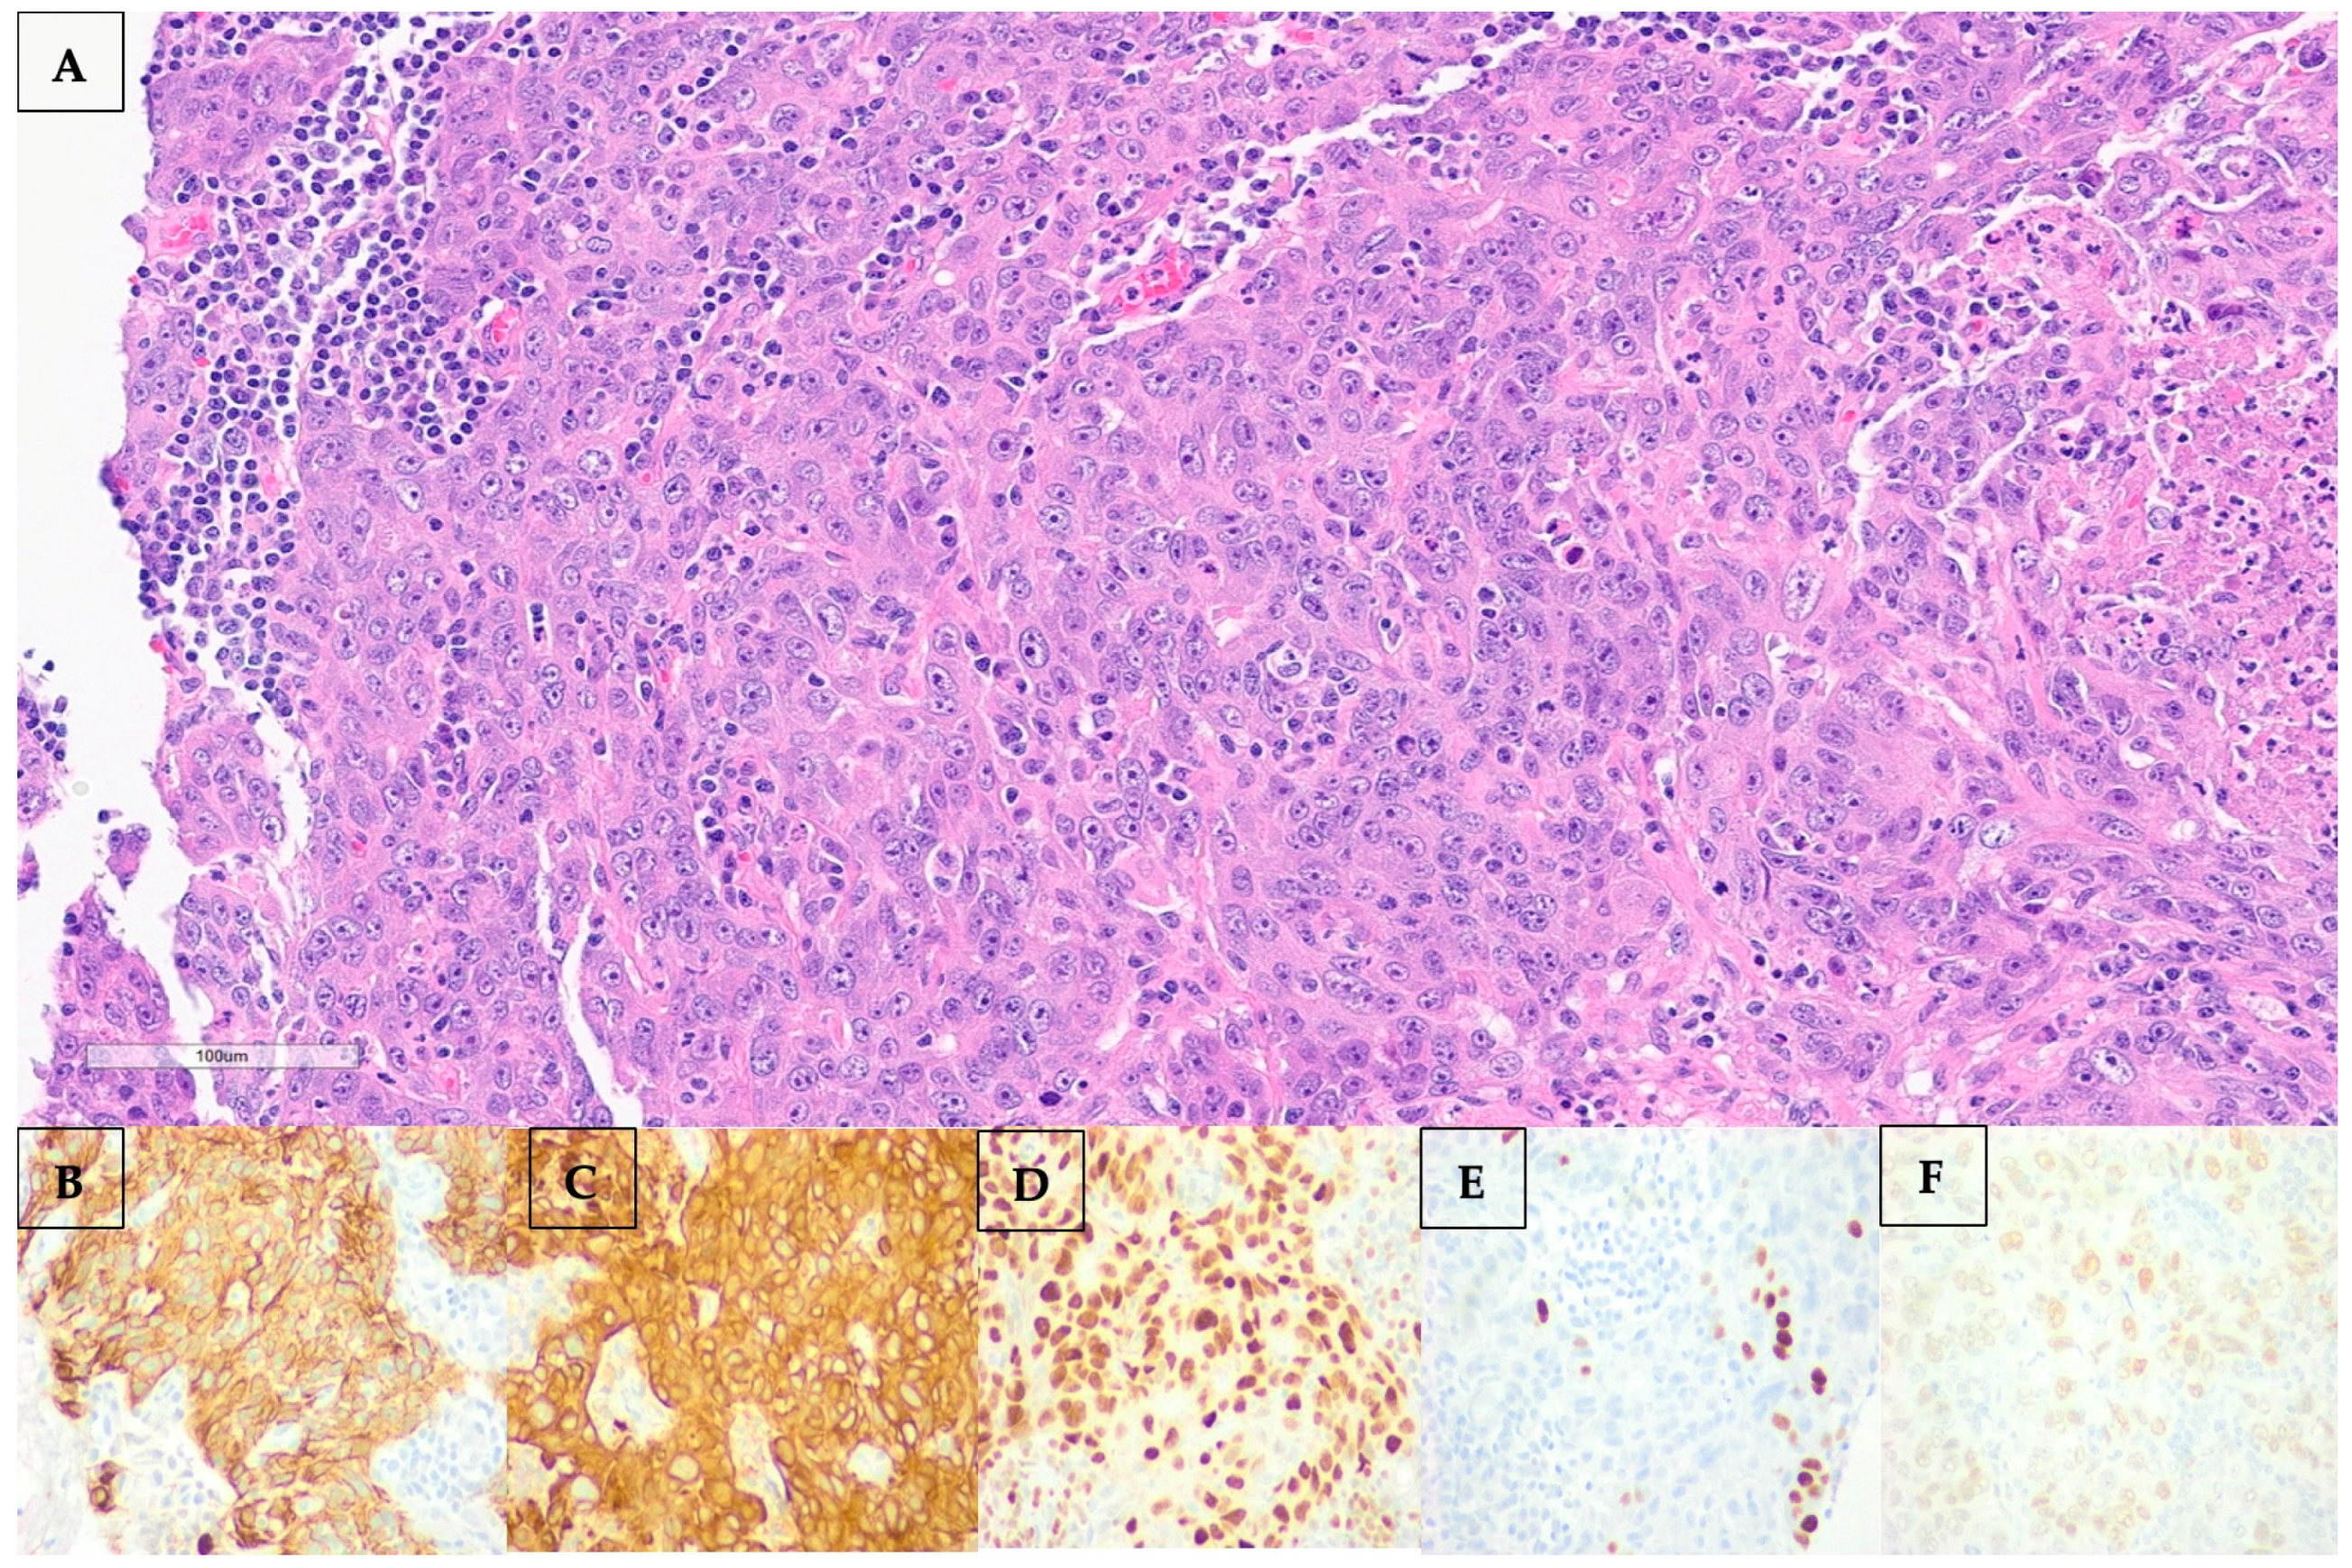

Percutaneous biopsy of the axillary node revealed a metastatic poorly differentiated carcinoma. Morphological examination and immunostaining could not conclusively distinguish between adenocarcinoma and squamous cell carcinoma. Histological and immunohistochemical images are shown in Figure 3. Of note, the neoplasm was negative for the following: CK20, TTF-1, Napsin, Synaptophysin, Chromogranin, S100, HMB45, Mart-1, Mammaglobin, GCDFP, ER, PR, HER2, CDX2, PAX8, and CD45.

Figure 3.

(A–F): (A) Hematoxylin and eosin (H&E) staining of the left axillary lymph node showing marked atypia, focally quite pick cytoplasm, focal necrosis, and mitotic figures. By immunostaining, the neoplasm stained positive for CK7 (B), AE1AE3 (C), diffusely positive for GATA3 (D), focally positive for p40 (E), and 20% positive for estrogen receptor (ER) (F).